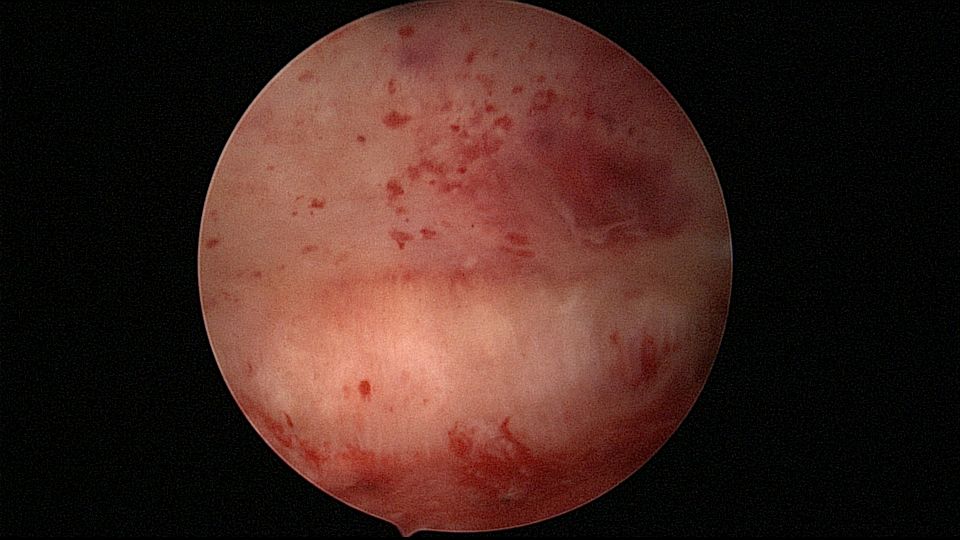

患者56岁,G2P1,顺产1次。安环16年,绝经1年,外院取环失败。宫颈外口及宫颈内口狭小质硬,分别用中弯钳及异物钳扩张,宫腔镜见宫颈管息肉2个,宫型环与宫壁嵌顿,异物钳取出,单级电针切除息肉送病检,病检结果为宫颈管息肉,宫腔未见其他异常。